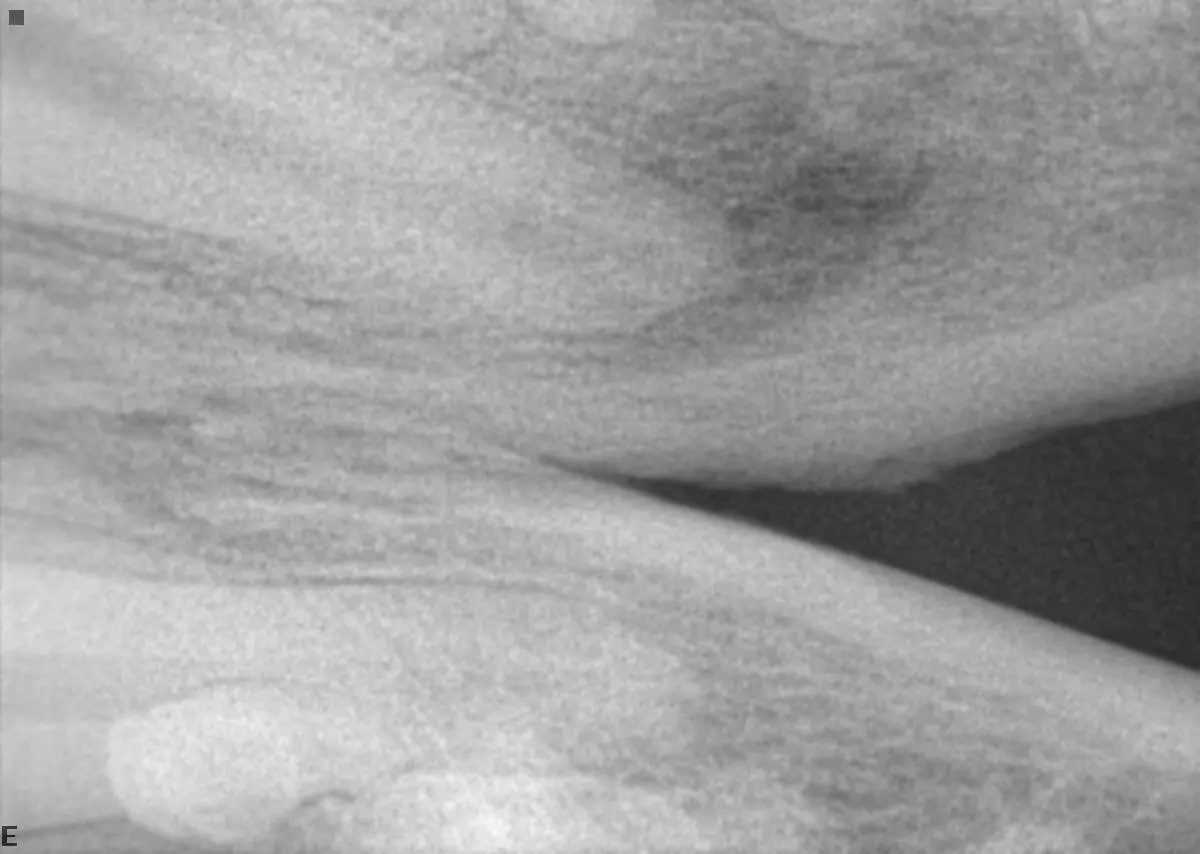

Generalized chronic contact mucositis/stomatitis that was treated with multiple rounds of antibiotics (unsuccessfully)